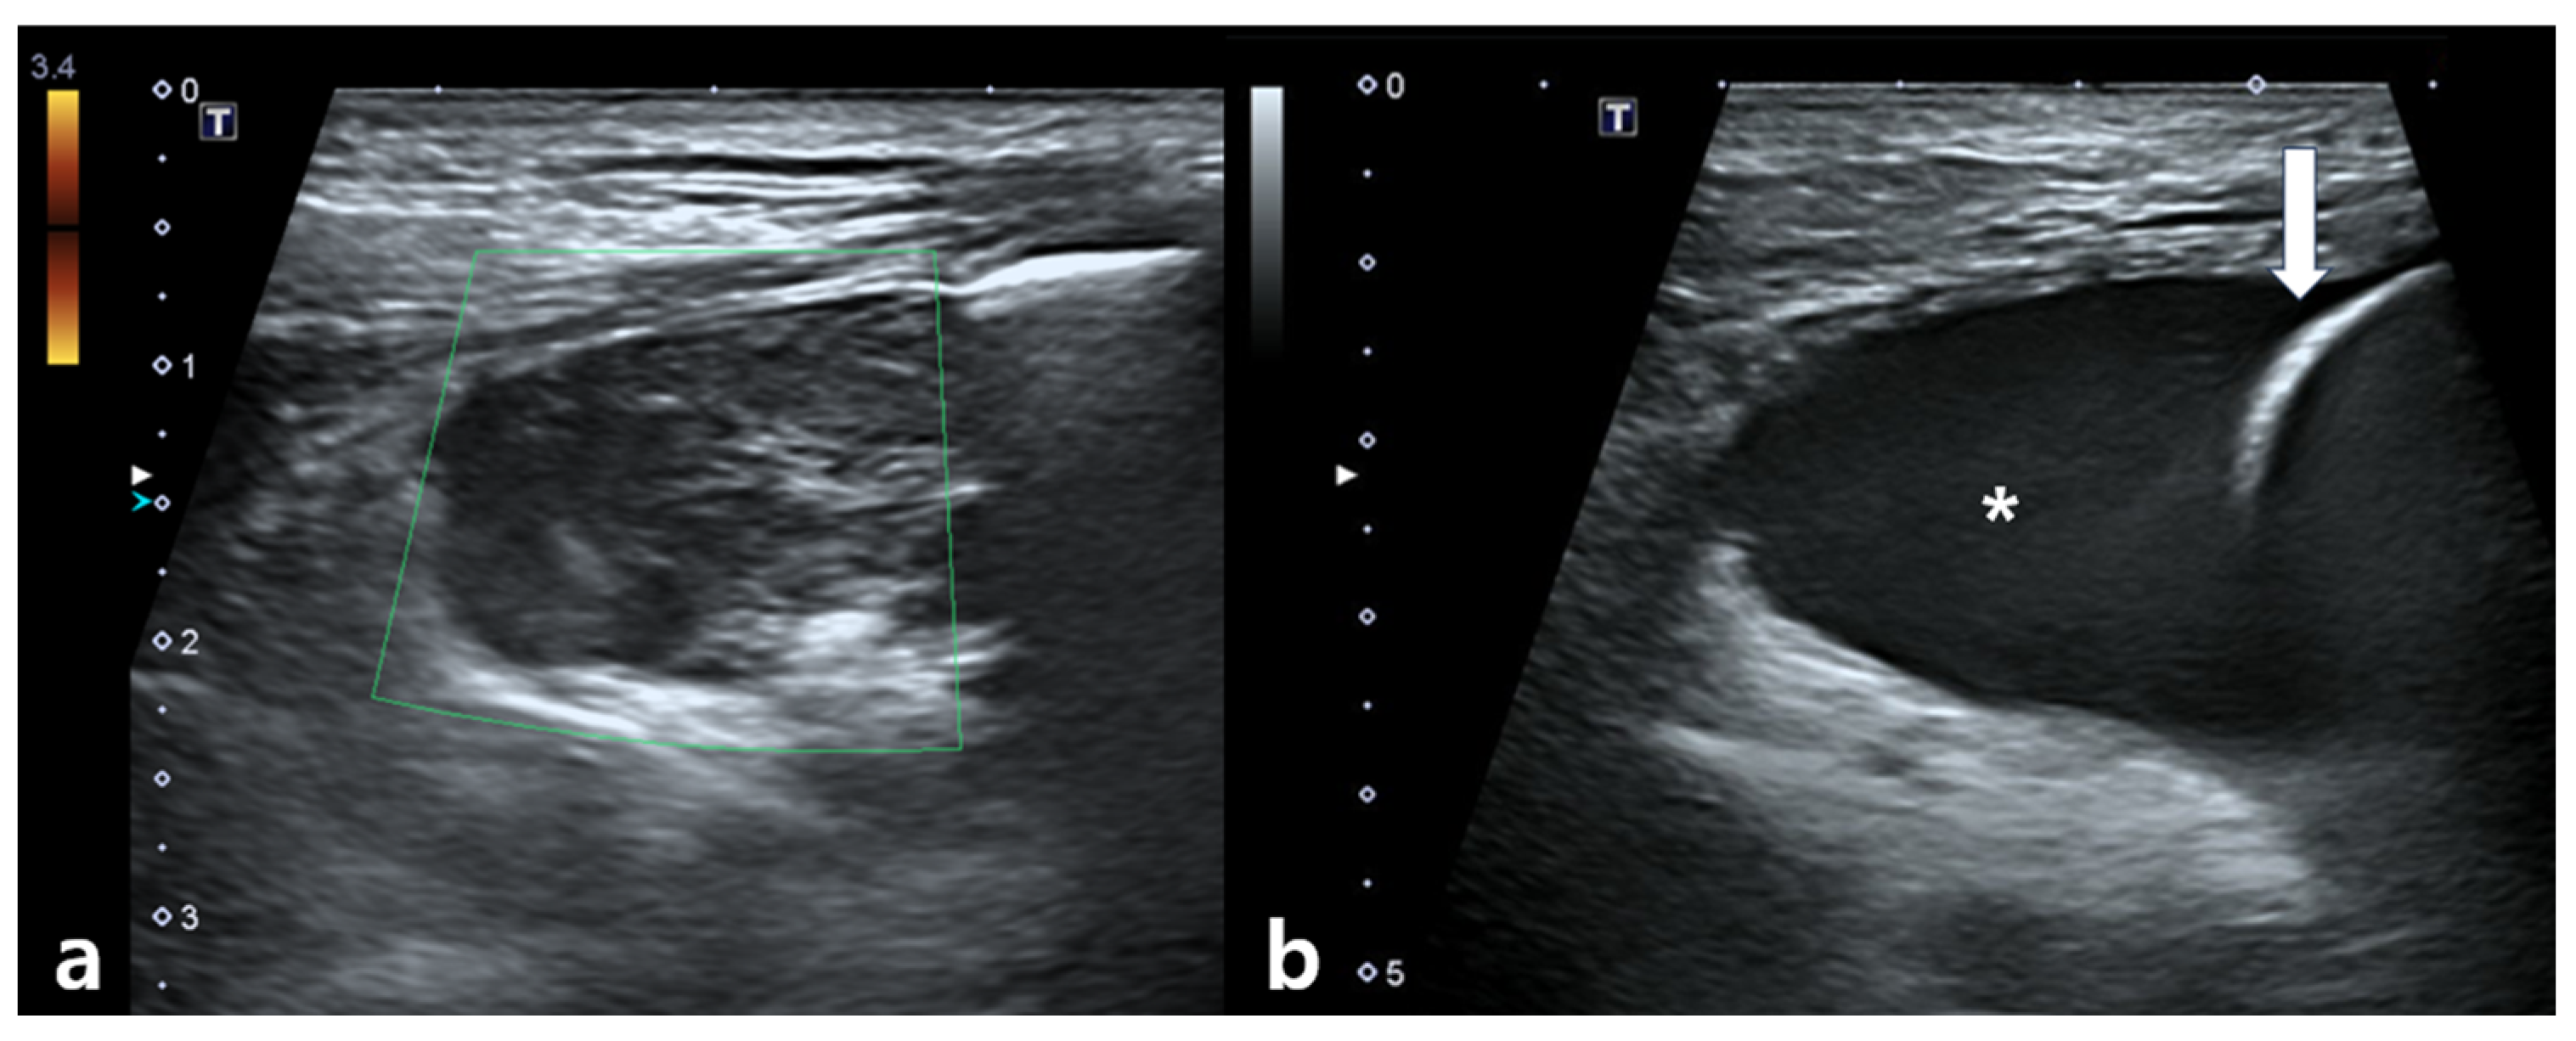

Figure 5. Thoracic ultrasonographic findings obtained 1 day after completion of the final fraction of stereotactic body radiotherapy. (a) A heterogeneous, hypoechoic mass can be detected adjacent to the irradiated mediastinal mass. No vascular flow is observed on color Doppler imaging. (b) Anechoic fluid accumulation is present between the lung parenchyma and thoracic wall, consistent with pleural effusion. The asterisk indicates fluid accumulation and the white arrow indicates the lung surface.

The dog remained clinically stable throughout the SBRT course. The dog completed all three planned SBRT fractions without treatment interruption and remained clinically stable under anesthesia during all sessions. However, the day after the final fraction (5 days after the first fraction), the dog developed acute dyspnea, characterized by increased inspiratory effort and mild open-mouth breathing. Clinical signs of anemia were also evident, as the mucous membranes appeared markedly pale, capillary refill time was prolonged to approximately 2.5 s, and the patient exhibited lethargy with reduced responsiveness to external stimuli. Hematologic testing revealed decreased platelet count (124 × 103/μL), red blood cell count (4.04 × 106/μL), hemoglobin (9.0 g/dL), and hematocrit (28.8%). To rule out an underlying coagulopathy, coagulation testing was performed, and the results showed that PT (10.4 s; reference range: 5–15 s), aPTT (29.2 s; reference range: 15–45 s), and fibrinogen concentration (2.7 g/L; reference range: 1–3 g/L) all remained within normal limits. Thoracic radiographs showed increased cranial mediastinal width (74.5 mm), swelling in submandibular and axillary regions, and pleural effusion (Figure 4). On palpation, the swelling in the bilateral submandibular and axillary regions was cool to the touch, soft, and pitting, with well-defined margins. There was no local warmth, erythema, or pain on palpation. The swelling was symmetrical and corresponded anatomically to the drainage area of the cranial vena cava, suggesting congestion secondary to venous compression rather than inflammatory or neoplastic infiltration. Thoracic ultrasonography revealed a heterogeneous, hypoechoic mass adjacent to the mediastinal lesion, with no detectable vascular flow signals on color Doppler imaging. Transthoracic echocardiography demonstrated a decreased left ventricular internal dimension during both diastole and systole, with preserved global systolic and diastolic function, and no evidence of structural cardiac abnormalities. Anechoic fluid accumulation was observed between the lung parenchyma and thoracic wall, consistent with pleural effusion (Figure 5). Based on the imaging and hematological findings, cranial vena cava compression secondary to tumor-related hemorrhage and hematoma formation associated with the irradiated mass was considered the most likely diagnosis. Other possible differential diagnoses included a necrotic portion of the tumor, abscess formation with inflammation, or a metastatic lesion.